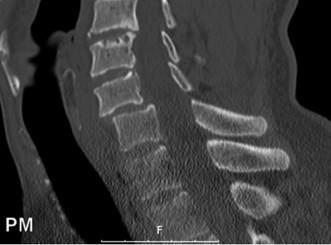

The diagnostic imaging workup for this patient spanned his initial presentation at age 15 and his subsequent return at age 20, providing a textbook illustration of the natural history of untreated isthmic spondylolysis. During his initial visit, standard weight-bearing anteroposterior (AP), lateral, and bilateral oblique radiographs of the lumbar spine were obtained. The lateral radiograph demonstrated a normal lumbar lordosis and preserved L5-S1 disc space height, with no evidence of anterior translation (spondylolisthesis). However, the oblique radiographs revealed the pathognomonic "collar on the Scotty dog" sign. The "Scotty dog" represents the posterior elements of the vertebra, where the nose is the transverse process, the eye is the pedicle, the front leg is the inferior articular process, and the neck is the pars interarticularis. A radiolucent line across the neck confirmed the presence of bilateral L5 pars defects.

Upon his return five years later, the imaging profile was drastically different. Standing lateral radiographs now revealed a Meyerding Grade 2 spondylolisthesis at L5-S1, indicating that the L5 vertebral body had translated anteriorly by 25% to 50% over the sacral promontory. Furthermore, there was a noticeable collapse of the L5-S1 intervertebral disc space, signifying advanced degenerative changes secondary to the altered biomechanics and chronic instability. We also meticulously measured the patient's spinopelvic parameters on a standing 36-inch scoliosis cassette. His Pelvic Incidence (PI) was measured at 65 degrees (high), which mathematically dictates a higher Sacral Slope (SS) and Pelvic Tilt (PT). A high PI is a known biomechanical risk factor for the progression of spondylolisthesis, as it creates a steeper lumbosacral shear angle, placing immense anterior translational force across the compromised L5-S1 segment.

Clinical & Radiographic Imaging Archive